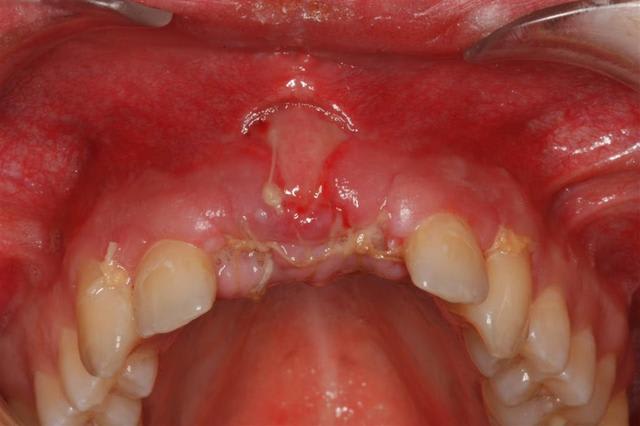

o.k. mais le trip reste le même que tu le fasses en une fois ou huit jours après. La bague de cica est déjà une mise en vitrine. D'autre part ce genre de truc ça gonfle tellement les premiers jours que ta patiente ne va pas sourire des masses ni même bouffer dans le secteur... Il faut relativiser d'autant plus qu'ici je me retrouvais short pour le calage primaire et tu noteras la classe II... La mise en place de la provisoire a eu lieu au retrait des sutures. Et il ne pourra pas s'agir d'une mise en charge, simplement d'une mise en vitrine.

Le didacticiel répondait à la question de Pluton qui se rendra vite compte que la mise en vitrine immédiate en zone prémaxillaire est un objectif peut-être souvent poursuivi mais plus rarement atteint. Mais peut-être qu'ailleurs l'herbe est plus verte ?